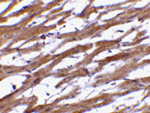

Immunohistochemistry of BAP29 in human heart tissue with BAP29 antibody at 10 ug/mL.